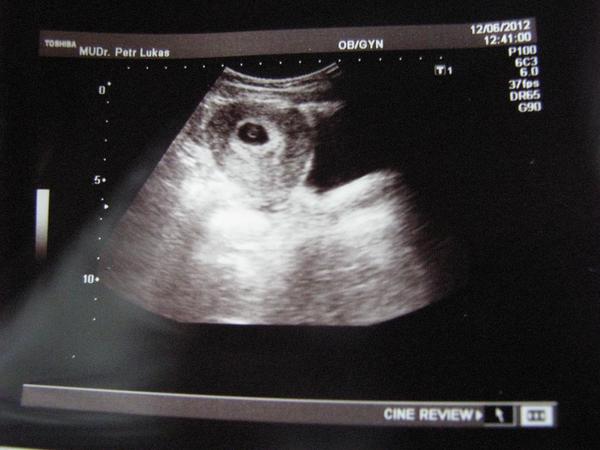

ahojte holčiny moje, dnes jsem byla u svého gyndaře a toto je náš první UTZ.

Mimísek má asi 7-8mm 😵

takže Vám všem posílá velkýýý pozdrav 😉 😵